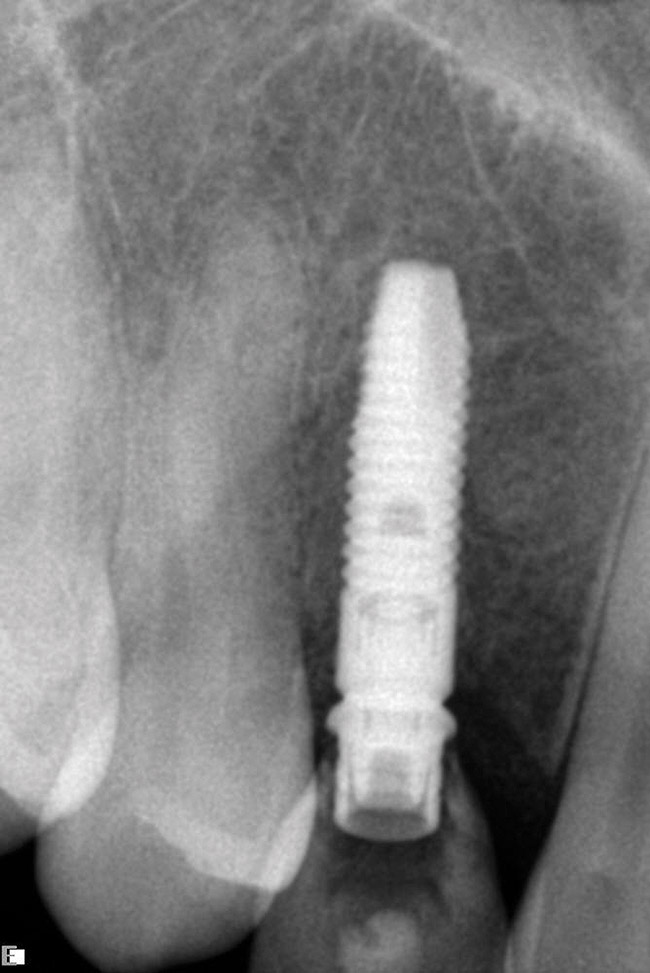

A 26-year-old woman presented with a history of trauma combined with an impacted maxillary right canine (No. 6), which was extracted in early childhood. Following two courses of orthodontic therapy—one in her early teens and the second in early adulthood—the area had reportedly been grafted approximately 9 months prior to her initial presentation to the author’s private periodontal practice. Clinically, the edentulous site appeared healthy, with significant keratinized mucosa in the canine position (Figure 1). A cone-beam CT scan revealed severe horizontal bone deficiency in the proposed implant position (Figure 2). Adequate bone height for implant placement was evident; however, the thinnest portion of the ridge measured approximately 0.45 mm in width. It was proposed that an augmentation be performed to facilitate implant placement, which the patient accepted.

Approximately 4 months after grafting, the patient returned for clinical and 3-D radiographic evaluation. The thinnest area of ridge width preoperatively was remeasured in approximately the same location, demonstrating a gain of about 4 mm (Figure 7). The treatment plan was to place a 3.5-mm x 13-mm implant with a computer-generated guide (SiCat, Sirona Dental, www.sironausa.com), eliminating an additional open surgical procedure. Planning included initial osteotomy preparation with single-use drills combined with a localized ridge expansion using narrow, tapered osteotomes. This was performed approximately 5 months after the augmentation procedure, achieving primary stability of the implant, facilitating a transmucosal healing approach (Figure 8 and Figure 9). Following each step of osteotomy preparation, a probe was inserted along the walls of the site to confirm the integrity of the buccal and palatal walls prior to implant insertion.

Figure 2 Cone-beam CT scan revealed severe horizontal bone deficiency in the proposed implant position.

Figure 2

Figure 7  3-D radiographic evaluation showed a gain of about 4 mm in the thinnest area of ridge width.

Figure 7